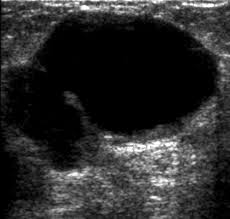

They can also occur in postmenopausal women taking hormone therapy. If the cyst comes back it may be evaluated again with mammogram and ultrasound and it can be drained again. On ultrasound a complex breast cyst will basically be treated in terms of internal echoes presence or absence of posterior enhancement thin septations and a thickened or irregular wall.

Breast cysts do not require treatment unless a cyst is large and painful or otherwise uncomfortable. On ultrasound a complex breast cyst will basically be treated in terms of internal echoes presence or absence of posterior enhancement thin septations and a thickened or irregular wall. A systematic review of the literature on sonographically detected complex breast cysts was carried. Management recommendations for complex cysts were 1-year follow-up in 13 patients 6-month follow-up in 148 sonographically guided aspiration in 82 aspiration with possible core biopsy in 62 and excisional biopsy in three. Your healthcare provider may want to perform a breast cyst aspiration or needle biopsy withdrawing fluid with a needle for analysis. Breast cysts dont require treatment unless a cyst is large and painful or uncomfortable. Not everyone is diagnosed with breast cysts and has treatment before pregnancy or childbirth. Complex breast cysts were estimated to be reported in approximately 5 of breast ultrasound examinations. Breast cysts can also be found in men although this is very rare.